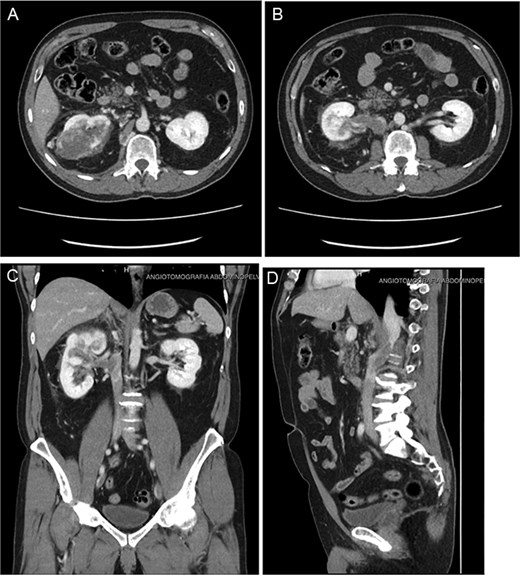

The authors present the case of a 60-year-old male patient with a recent diagnosis of T2a melanoma on the back, with no indication for adjuvant therapy, who underwent an abdominopelvic computed tomography with an incidental finding of a hypervascular solid mass in the right lower renal pole, compatible with an organic lesion measuring 8.5 × 7 × 8 cm invading the renal vein and the azygos vein, with intrathoracic extension (Fig 2A–D). The patient presents a vascular anomaly characterized by agenesis of the retrohepatic portion of the IVC. The hepatic veins drain directly into the right atrium, while the azygos vein serves as an alternative venous pathway, draining into the superior vena cava. A thrombus extends through the azygos vein into its intrathoracic portion.

(A–D) Abdominopelvic contrast-enhanced computed tomography prior to neoadjuvant therapy showing a lesion in the right kidney with associated mural thrombus extends through the azygos vein in the sagittal section.